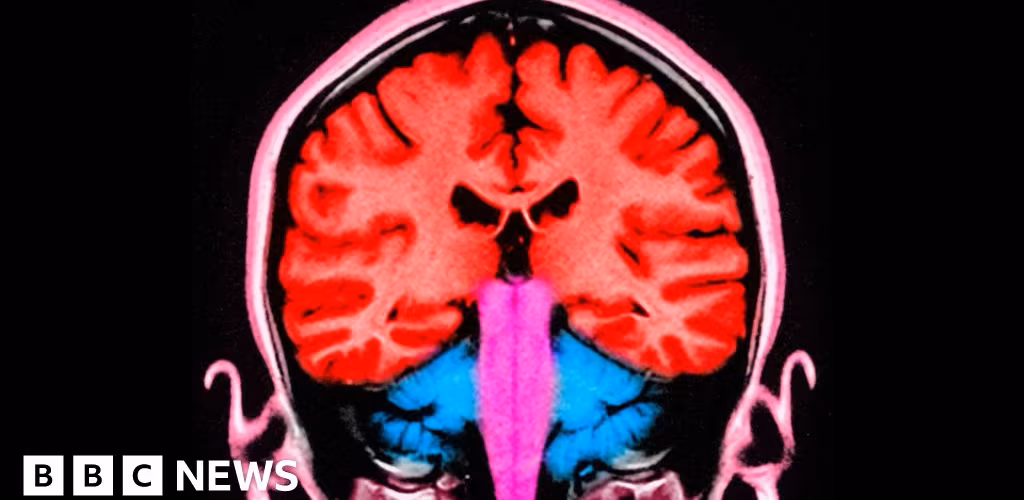

Can a pulse of electricity to the brain make us less selfish?

Scientists have discovered how to make people less selfish - slightly and temporarily - by stimulating two areas of the brain.